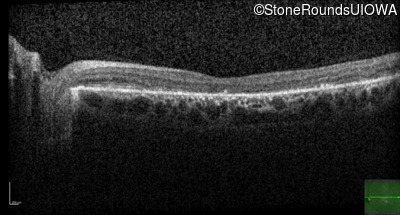

All three of the cardinal ophthalmic features of Mendelian macular dystrophies are present in this patient. The most striking features of the fundus exam are the numerous yellow flecks at the level of the RPE. Flecks are most commonly seen in AR Stargardt disease and pattern dystrophy although they may be seen in some of the rarer Mendelian maculopathies as well. The visual acuity in patients with AR Stargardt disease is often "worse than the fundus looks" while the acuity in pattern dystrophy is often quite good despite extensive flecks. The pedigree of this patient is compatible with ABCA4-associated Stargardt disease and the better than expected acuity is attributable to foveal sparing (see below). The onset of reduced acuity at age 10 is much more characteristic of ABCA4 disease than pattern dystrophy. Another feature present in this patient that is very frequently seen in Stargardt disease is peripapillary sparing. However, this sign can be seen in pattern dystrophy as well. When central atrophy is present in ABCA4-associated Stargardt disease it often somewhat shiny (which is uncommon with the geographic atrophy of pattern dystrophy or age-related macular degeneration). Some patients with ABCA4-associated Stargardt disease can have some preservation of the fovea giving a zonal "bullseye" appearance to the center of the macula. Sometimes this preservation is associated with preserved acuity as in this case. The outer nuclear layer (ONL) is much thinner than normal on OCT, indicative of photoreceptor loss. This is associated with a thinning of the ellipsoid zone which is usually many times brighter and thicker than the external limiting membrane (ELM). These two lines are essentially equal in intensity in this patient. The foveal sparing is seen on OCT only as a small bit of retinal convexity in the center of the atrophy coupled with a small bit of residual RPE flanked by bare Bruch's membrane. The presence of a robust I2e isopter on Goldmann perimetry places this patient in the least severe half of all Stargardt patients (see Schindler, et al., 2010). Most patients with ABCA4-associated disease are somewhat myopic as is this patient. Stargardt patients also tend to perform very poorly on pseudoisochromatic plates, even when their acuity is still fairly good as it is here.